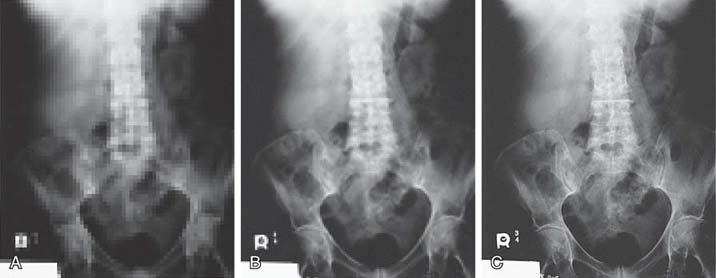

Spatial resolution in digital imaging is primarily limited to the size of the pixel; however, when measuring an imaging system's ability to resolve small objects, it is important to understand the concept of spatial frequency and its relationship with spatial resolution. Spatial frequency can be defined by the unit of line pairs per millimeter (lp/mm). A resolution test pattern is a device used to record and measure line pairs (Fig. 4-6). Anatomic details are composed of large and small objects, and radiographic images display these details as variations from white to black brightness levels. Small objects have higher spatial frequency, and large objects have lower spatial frequency. It is more difficult to accurately image small anatomic objects (high spatial frequency) than to image large ones (low spatial frequency). An imaging system that can resolve a greater number of lp/mm (higher spatial frequency) has increased spatial resolution (Fig. 4-7). In digital imaging systems, the ability to resolve or demonstrate a specific spatial frequency is directly impacted by the size of the pixel. The images of the wrist (Fig. 4-8) demonstrate the impact that pixel size has on the spatial resolution visualized in an image.

FIG. 4-8 Images showing how pixel size affects spatial resolution. A, Image with 20 pixels/cm; therefore, the pixel size is larger, and the spatial resolution is poor. B, Image with 40 pixels/cm. C, Image with 100 pixels/cm; therefore the pixel size is smaller than that in images A and B, and the spatial resolution is improved. (Courtesy of Andrew Woodward.)